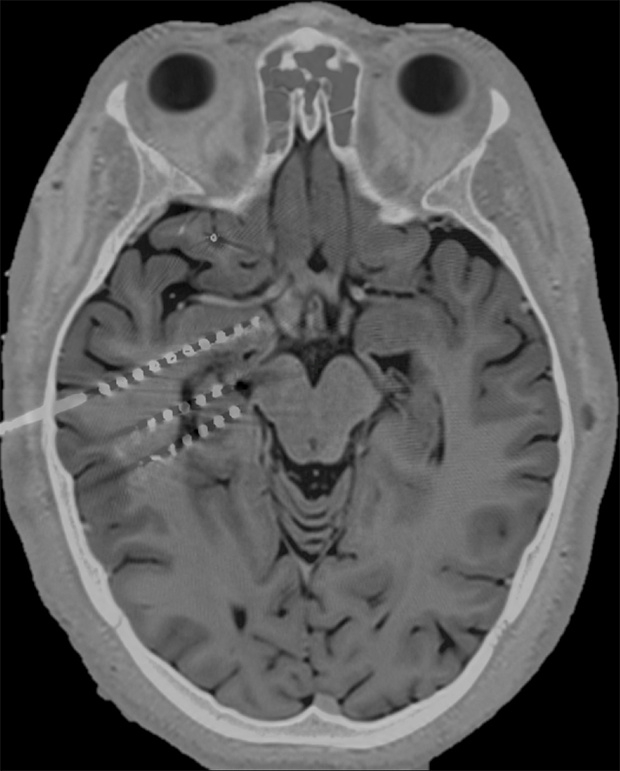

核磁共振和 CT 扫描结果显示,电极会刺激杏仁核(上)、海马体前部(中)和中部(下)